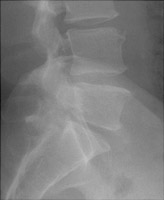

Spondylolysis refers to failure of fusion of the pars interarticularis, most often at the lower lumbar spine. This is usually a congenital defect, although it may occasionally be post-traumatic. The process may affect one or both sides of the spine. Oblique radiographs are best for the detection of this abnormality.

- Click on the image for a larger versionAOblique radiograph of the lumbar spine. This shows a pars defect.